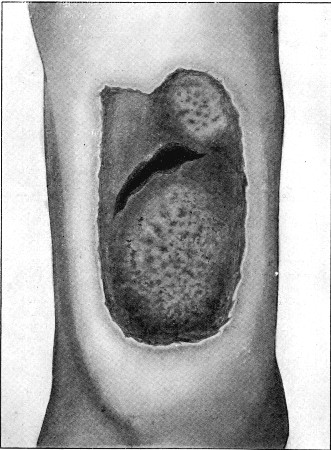

25b. Prolapsed Omentum77

89. Impaction of Omentum in Exit Wound of Abdominal Wall421